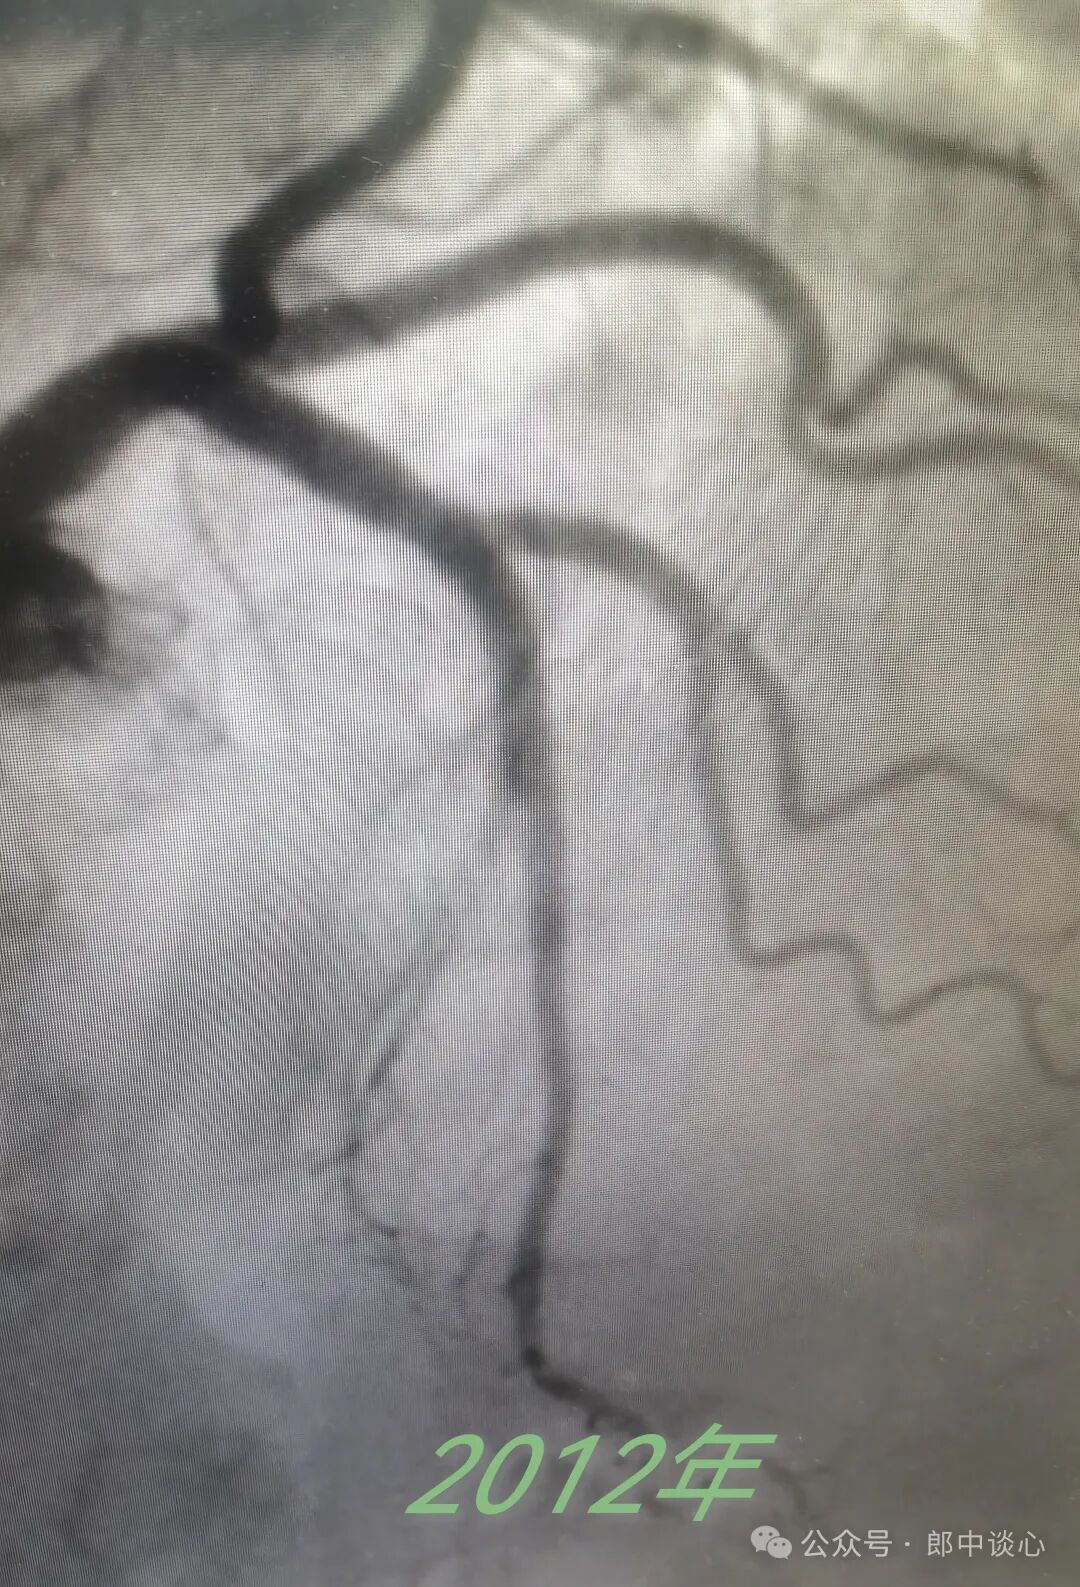

他在2012年前就有支架植入史,我在电脑上还能看到他在2012年、2013年做的造影。

看起来,当时的左冠还不错。